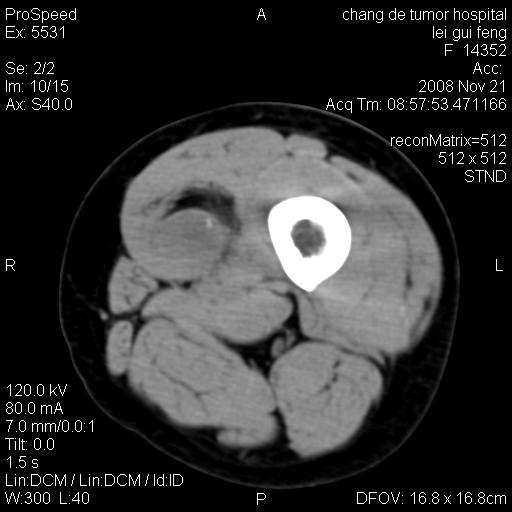

标题: CT16807:女 41 无不适 [打印本页]

标题: CT16807:女 41 无不适

考虑皮样囊肿可能性大

血管瘤可能

血管瘤

血管瘤可能性大!

黏液瘤或表皮杨囊肿

不排除横纹肌肉瘤可能。

血管瘤可能性大或畸胎瘤

考虑脂肪肉瘤

考虑血管瘤可能性大;不排除肉瘤可能。建议行活检。

脂肪肉瘤?

双是软组织肿瘤,病灶内多发钙化,另可见多量脂肪密度影,考虑畸胎瘤,血管瘤,不除外其他